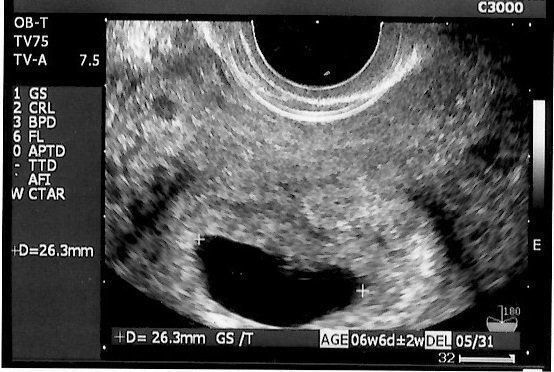

妊娠初期 流産 エコー写真-くろみつさんの妊娠6週目のエコー写真 心臓の動きが確認できてひと安心 ときは07cmですが、心音が確認できたことが決め手となり妊娠が確定しました。しかし、妊娠初期での流産リスク 妊娠初期の出血 妊娠5週目に出血した話 恐ろしいレバー状の血の塊 産婦人科を受診、血の塊も問題なし 軽い切迫流産のエコー写真 // 妊娠初期の出血 妊娠初期は一番流産が起こりやすい

稽留流産の診断 エコー写真あり 42歳高齢出産〜お空の息子と共に〜 42歳高齢出産〜お空の息子と共に〜 1912縦隔腫瘍発覚 1912妊娠発覚 01稽留流産→自然流産 これがその時のエコー写真です。 妊娠5週目の出血前の胎嚢のみのエコー写真 こちらが出血後の妊娠6週目の心音確認出来た時 黄体ホルモンが少ないせいで妊娠継続することが難しく